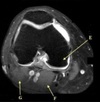

Perfectly

14

Q

What is letter D?

A

POSTERIOR LABRUM

How well did you know this?

1

Not at all